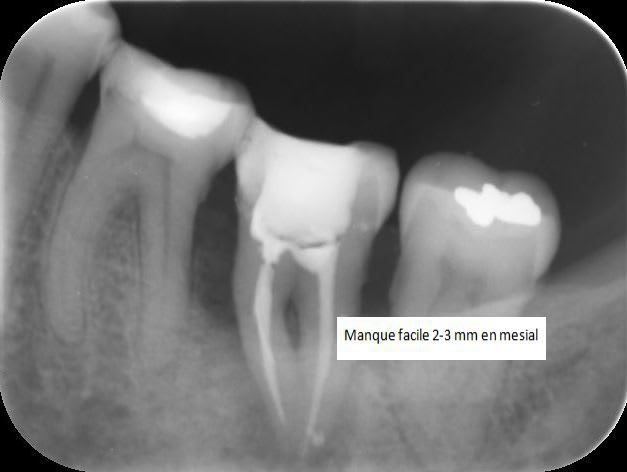

Lesion endo paro bdwn58 - Eugenol

J 0 obturation bof.. - Eugenol

J   3 mois  bonne surprise ya7tbg - Eugenol